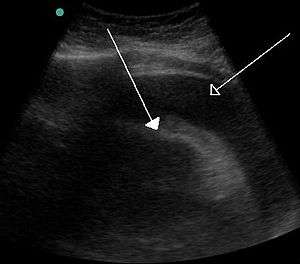

A very large hemorrhagic pericardial effusion due to malignancy as seen on ultrasound. closed arrow: the heart, open arrow: the effusion- Pericardial effusion due to malignancy. Note bulbous heart and primary lung cancer in right upper lobe.